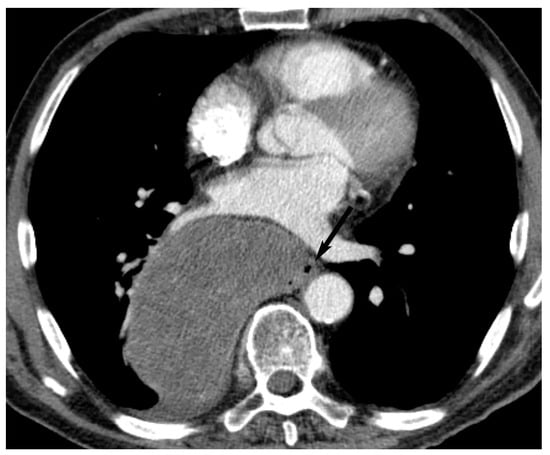

7. Germ Cell Tumors

9. Hypervascular Lesions